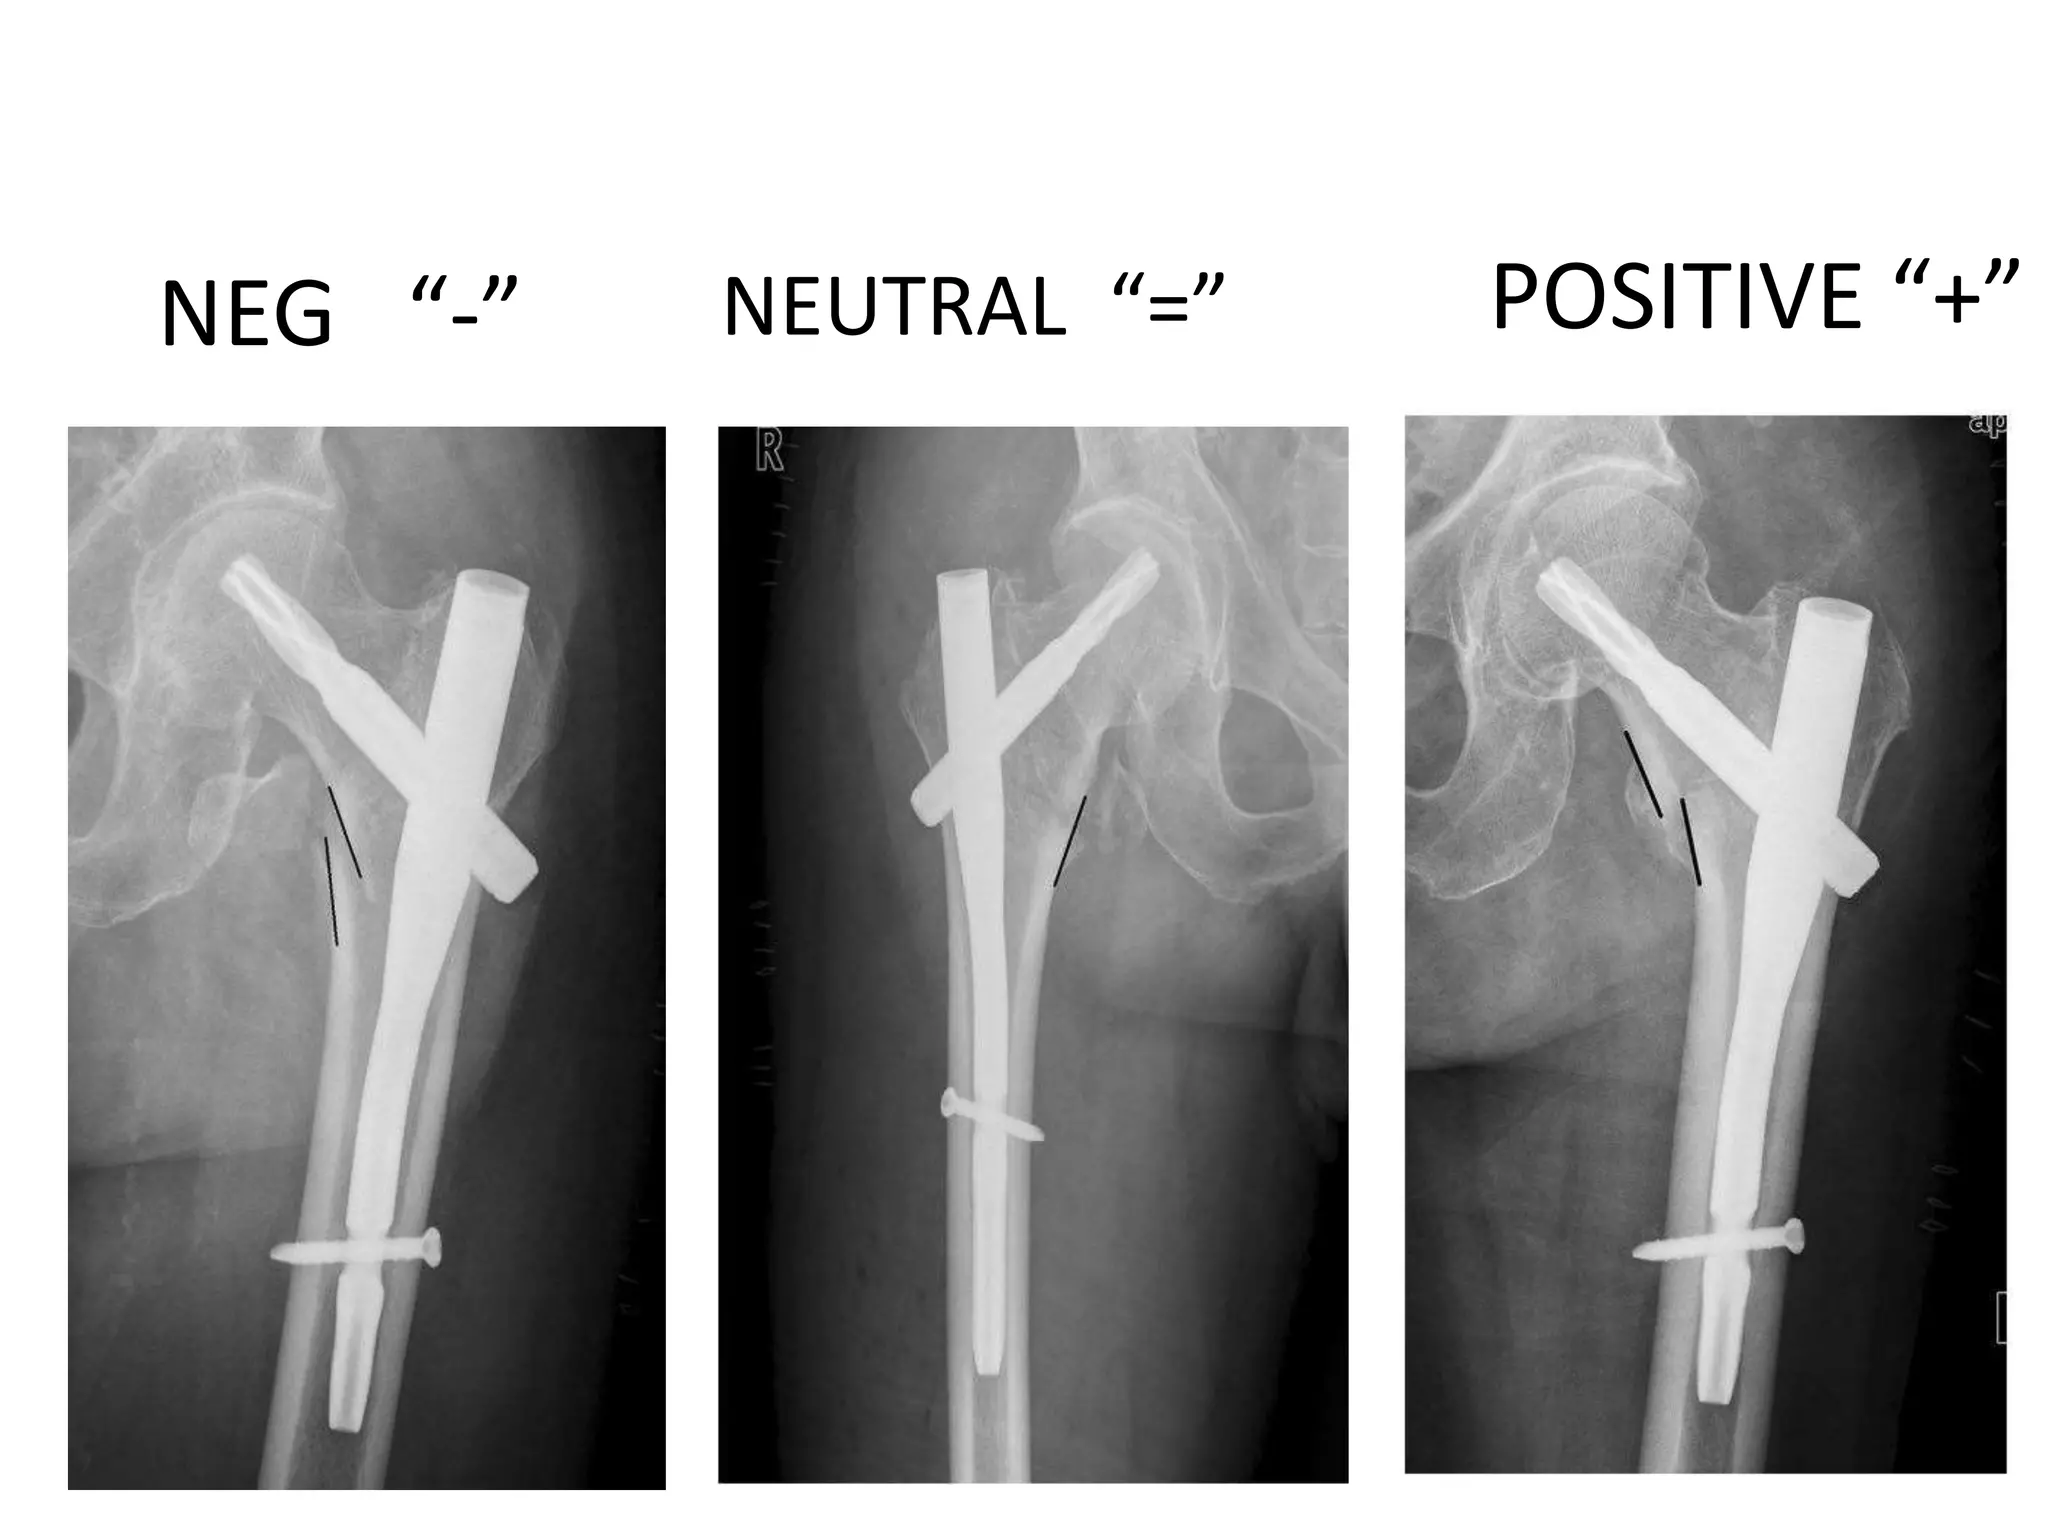

Positive medial cortex support (PMCS):

Medial calcar beak is outside the

femoral canal and may slightly overlap

the distal femur.

Negative medial cortex support (NMCS):

the head–neck fragment is displaced

laterally to the upper medial edge of the

shaft fragment

NEG “-” POSITIVE “+”

NEUTRAL “=”

Positive medial cortexsupport (PMCS): Medial calcar beak is outside the femoral canal and may slightly overlap the distal femur. Negative medial cortex support (NMCS): the head–neck fragment is displaced laterally to the upper medial edge of the shaft fragment

NEG “-” POSITIVE“+” NEUTRAL “=”